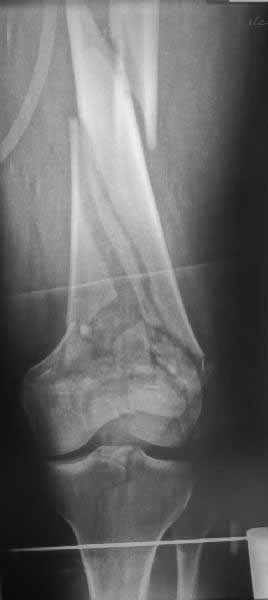

использовать. В приложении пример недавней операции, C3, открытая

репозиция, фиксация мыщелков спицами и винтами, ретроградный синтез

большеберцовым гвоздем 10,5 мм диаметром, винты 5 мм.